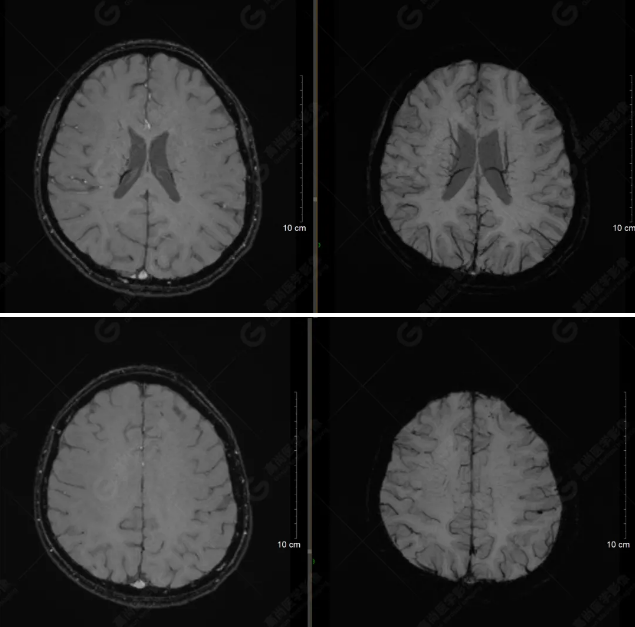

(左側(cè)為薄層原始圖像,右側(cè)為后處理5mm圖像)

SWI序列影像表現(xiàn)及診斷

左側(cè)額底及左側(cè)顳葉內(nèi)見多發(fā)斑點狀極低信號影??紤]額顳葉多發(fā)腦挫傷伴微出血、含鐵血黃素沉著,左側(cè)乳突骨折、乳突內(nèi)積血。討論:1、SWI利用不同組織間磁敏感的差異成像并將其放大,通過檢測病灶中的靜脈分布、出血灶和礦物質(zhì)沉積等,有效改善了相關(guān)疾病的診斷,主要應(yīng)用于中樞神經(jīng)系統(tǒng)。2、根據(jù)磁距圖像和相位圖像表現(xiàn),對于鑒別顱內(nèi)出血及鈣化有一定程度的價值,用于彌補(bǔ)MRI對鈣化顯示的不足。